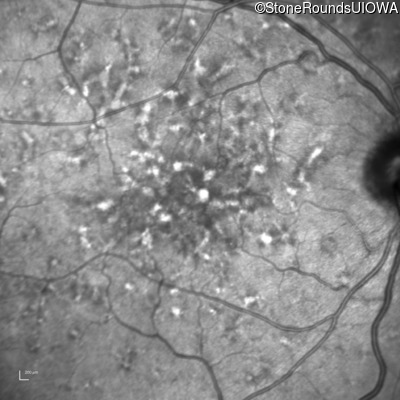

Pattern Dystrophy (IIC)

Age at visit: 49 years

This 49 year old man was first told he had a fundus abnormality on a routine eye exam at age 34. Ten years later he noticed some distortion just superior to fixation.

Pattern Dystrophy PRPH2 Gln239Stop CAG>TAG   AD